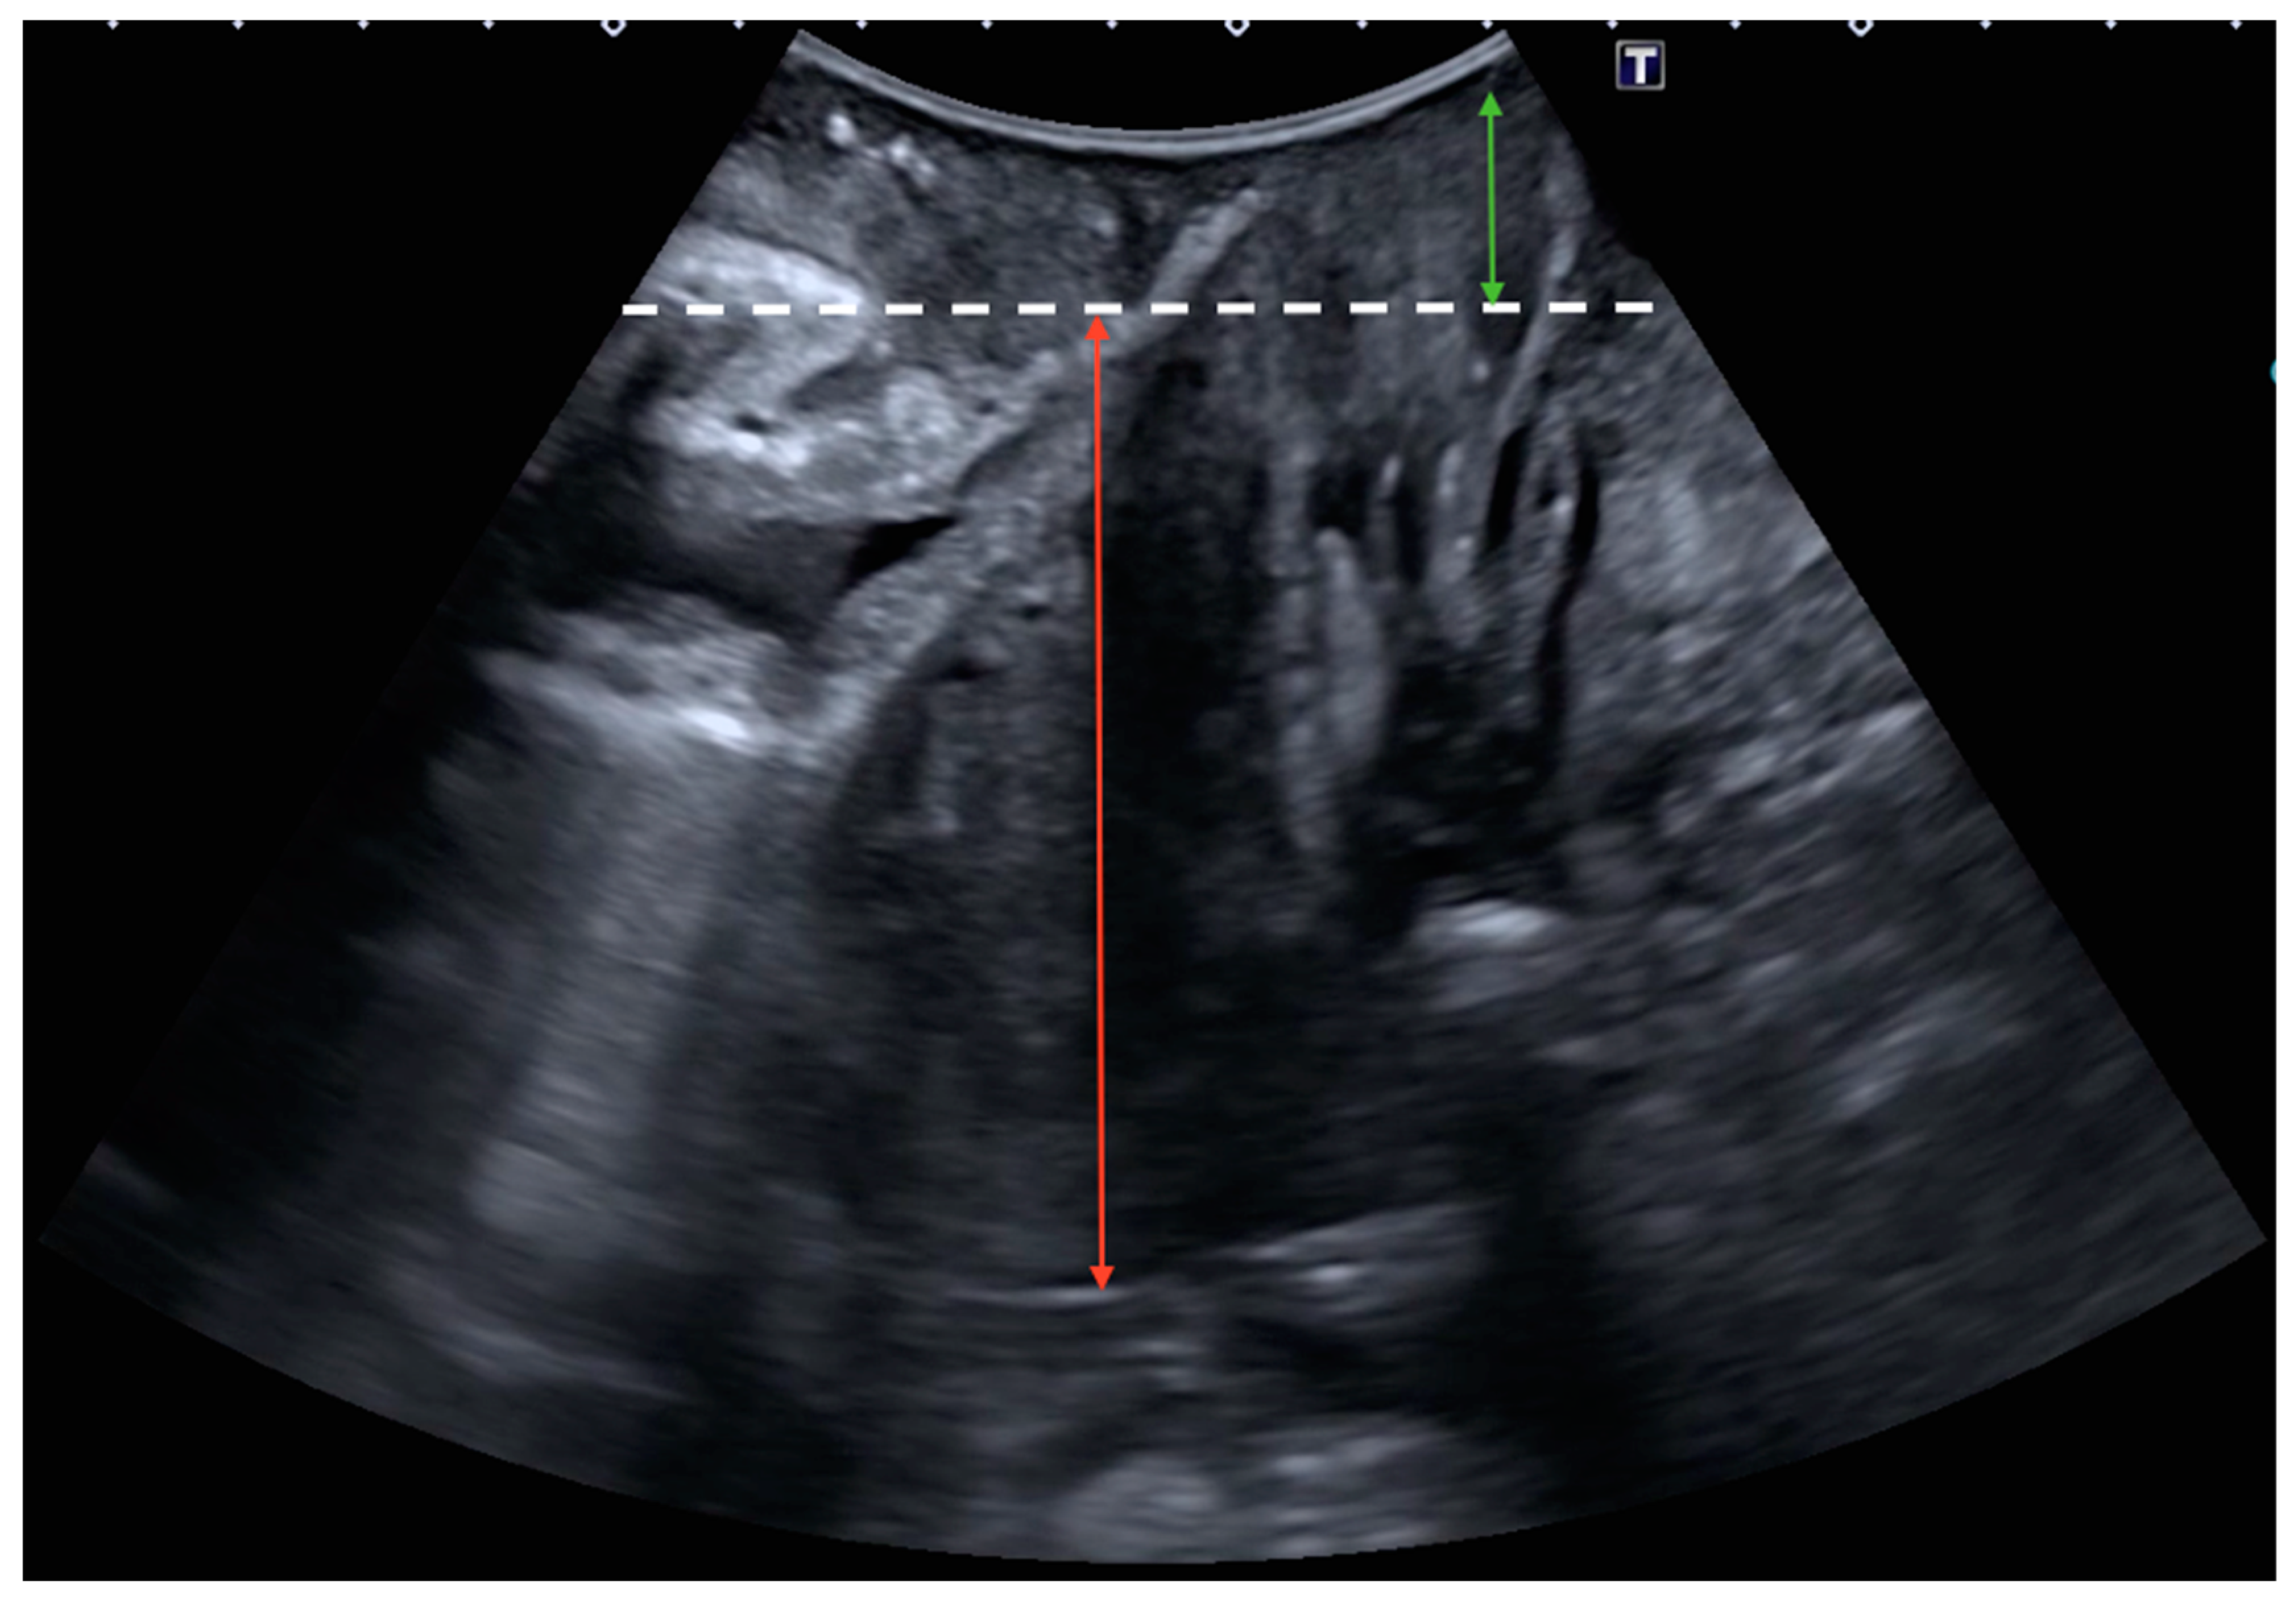

2.2. Ultrasound Examination